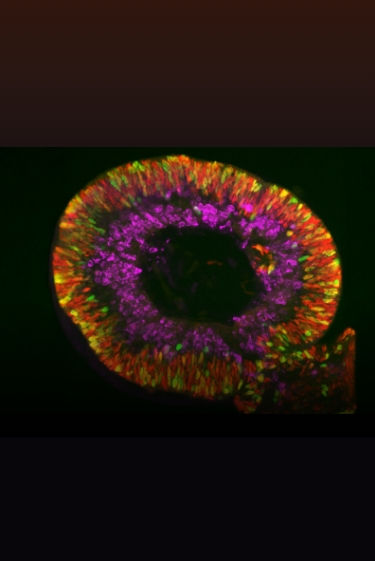

כדי ליצור פְּרִיוֹן מלאכותי של אדם במעבדה, ביטאו החוקרים את החלבון התקין בחיידקים והפיקו אותו מהם. לאחר מכן הוסיפו לחלבון הנקי כמות קטנה מאוד (0.5 אחוז) של פריון מחולה קרויצפלד-יעקב. התברר שהפריון החדש שיצרו בדרך זו שונה בצורתו מהפריון המקורי מחולה. כמו כן, גילו החוקרים שליצירת הפריון דרושה תוספת של מולקולה ממשפחת הגנגליוזידים, שהם נגזרות של חומצות שומן המשתתפות בבניית קרומי התא, וייתכן שהם מעורבים גם בהתקדמות מחלת אלצהיימר. ייתכן שהמולקולה דרושה גם לַשינוי המוביל לצורת הפריון באדם, אך החוקרים לא המשיכו לחקור בכיוון זה.

בשלב הבא החוקרים לקחו עכברים שהונדסו גנטית כך שיבטאו במוחם את חלבון הפריון של האדם, והזריקו למוחם את הפריון המלאכותי או פריון קרויצפלד-יעקב המקורי שהופק מחולה והשוו את יכולת השכפול של שני הפריונים ואת הנזק לעכברים. שני הפריונים הדביקו את העכברים וגרמו למחלה קטלנית. שימוש בתמציות מוח מעכברים אלה הדביק עכברים נוספים, מה שהוכיח שהפריון המלאכותי, כמו הפריון המקורי, מתרבה ומידבק. בנוסף, בדיקות ביוכימיות גילו, כי תמציות המוח של עכברים שהודבקו בפריון המלאכותי הכילו פי 100 עד פי 1,000 יותר פריונים פעילים מאשר תמציות המוח של עכברים שהודבקו בפריונים שנלקחו מחולה. כלומר, די בכמות קטנה פי 100 עד פי 1,000 של תמצית מוח ובה פריון מלאכותי לעומת הפריון המקורי כדי להדביק במחלה.

לבסוף, החוקרים השוו את הנזק המוחי שנגרם לעכברים השונים מהפריון המלאכותי ומשני תתי הזנים של הפריון המקורי שהתקבלו בניסוי. בעוד שכל אחד משלושת הפריונים גרם לנזק רב למוח, כל תת-זן גרם לנזק באזורים אחרים במוח. הפריון המלאכותי גרם לנזק הנרחב ביותר. החוקרים ציינו במיוחד את הנזק לאזור CA3 בהיפוקמפוס – אזור האחראי במידה רבה על למידה וזיכרון, ונפגע גם במחלה ניוונית הדומה למחלה פריונית – מחלת אלצהיימר.